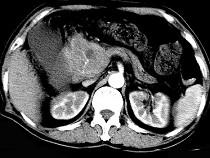

问题 男,50岁,黄疸进行性加重、腹部胀痛不适、食欲减退、体重减轻、上腹部可触及肿块,CT如图,最可能的诊断为()

选项 A.急性胰腺炎 B.慢性胰腺炎 C.胰头癌 D.腹膜后淋巴瘤 E.转移瘤

答案 C